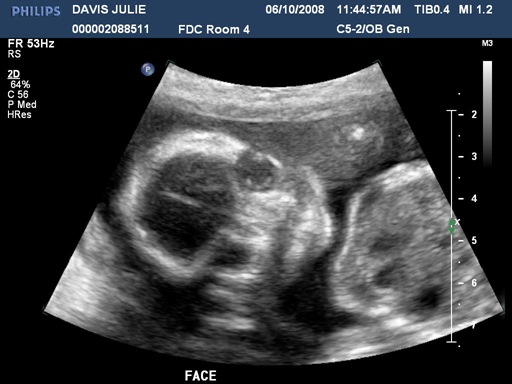

We went in for our first ultrasound today. It was a fun experience getting to see our first glimpses of the little life that is growing inside Julie’s belly. The ultrasound equipment at Winnie Palmer hospital is much better than when we had ultrasounds with our two daughters. But that was several years ago also. Seeing our baby’s little fingers, arms, heartbeat and all of the movements was a really neat experience. We also found out that we are having a little boy! We were all kinda hoping for that. Laurel and Marybeth were running around quoting a line from “Lady and the Tramp“…”Oh boy, it’s a boy! Oh boy, it’s a boy! Oh boy, it’s a boy!”

So…what does our baby look like now? Here are the five pics the hospital gave us (three are after the break). Also…if you don’t want to see the proof of “boyhood”, avoid the last picture.